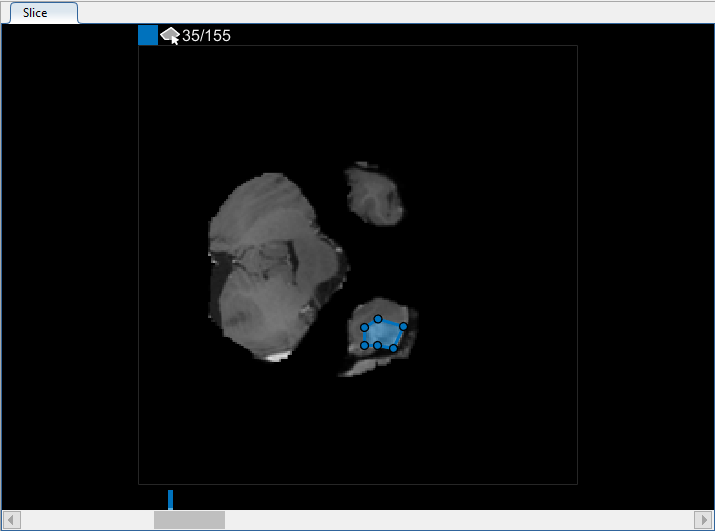

Можно также просмотреть каждый срез объема в панели Среза. Используйте ползунок в нижней части панели, чтобы переместиться от среза до среза. Вы видите опухоль на срезе 35 через срез 88. По умолчанию панель Среза отображает объем, ориентированный вдоль оси X-Y, но можно изменить это использование кнопки в разделе Orientation панели инструментов на вкладке Segmenter. Панель Среза также, где вы используете инструменты для рисования, чтобы задать маску.

В панели Среза перейдите к срезу, где объект сначала появляется, срез 35, и чертите схему вокруг объекта. В данном примере используйте инструмент для рисования Многоугольника. Щелкните, чтобы создать вершину, затем переместите курсор и щелкните еще раз, чтобы создать вторую вершину прямой линией, соединяющей их. Продолжите этот процесс, чтобы создать связанную линию. Чтобы добавить дополнительные вершины после того, как вы закончите чертить, дважды кликните на ребре ROI.

Чтобы использовать интерполяцию, необходимо сначала вручную задать область на двух срезах. Вы уже задали область на первом срезе, где объект появляется, срез 35. Используйте тот же процесс, чтобы задать область на последнем срезе, где это появляется, срез 88. Приложение помещает две панели сверху ползунка, с помощью цвета, сопоставленного с меткой, чтобы указать на срезы с ROI.